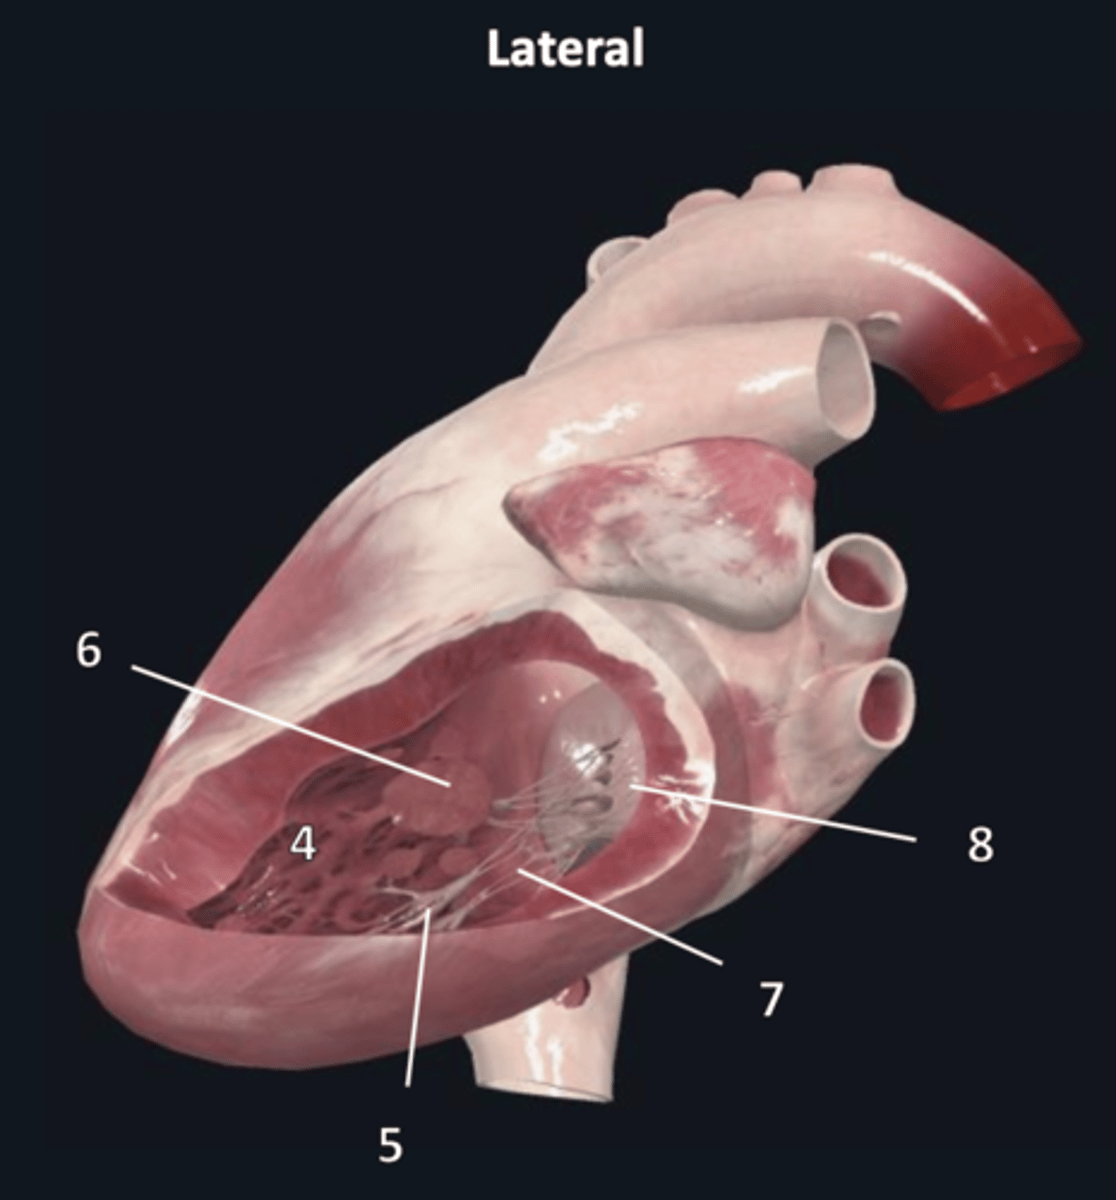

left atrium

1

left auricle

2

left ventricle

3

trabeculae carneae

4

inferior papillary muscle

5

superior papillary muscle

6

chordae tendineae

7

left atrioventricular valve

8 (opening)

aortic semilunar valve

9 (opening)